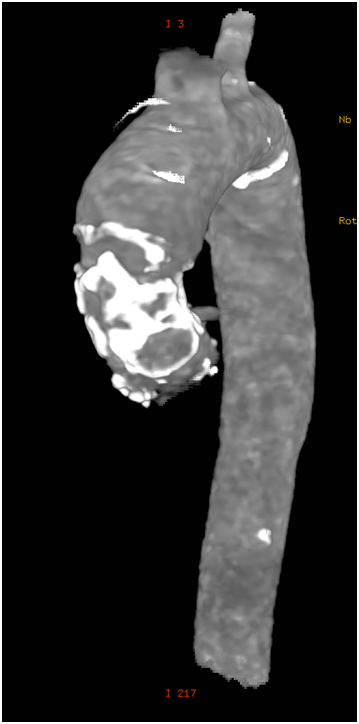

79 y old male patient, known to have diabetes mellitus, end stage renal failure and chronic obstructive pulmonary disease, this patient had aortic valve replacement (AVR) 15years prior, but because of infective endocarditis 7years ago, he underwent a redo AVR (Aortic valve Bioprosthesis) using a 25mm cry preserved aortic homograft implanted as a full root in another hospital. Patient was admitted with severe heart failure and pulmonary edema. His Echocardiogram showed severe AR (Figure 1). Patient was treated aggressively with anti-failure medications. The case discussed in heart team and both options AVR vs TAVI were raised in this high risk patient, with STS score 18. Both the heart team and Family preferred TAVI, According to sizing application this homograft valve will fit with Size 29mm Core Valve, The CT-scan measurements showed an aortic annulus size 21-25mm at different level, Perimeter range from 71-73, 3mm, Aortic valve area 2.9 cm2, and a heavily calcified a tube-like aorta (Figure 2). No clear sinus or junction was seen by CT. A trans-femoral approach for Valve in Valve was used. A 29 mm Medtronic Core valve was deployed and the landmark was the calcium in the root. Unfortunately, it migrated up-ward most probably due to the rigidity of the homograft tube and no real narrowing or calcified leaflet to anchored the valve (Figure 3). Therefore we used another 29 core valve and deployed it through the first one which was well seated in ascending aorta as support. This method of support was very successful for final deployment (Figure 4). It was similar to the melody valve deployment in treating pulmonary regurgitation. There was no aortic regurgitation by Echocardiogram (Figure 5). Patient was very stable and discharged home after 48hours.

Figure 3 The Core Valve migrated up to the ascending aorta immediately after its deployment.